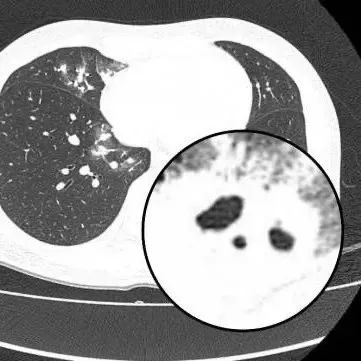

胸部CT显示其双肺多发感染

伴多发空洞形成

医生查房时,捕捉到CT上形似“鬼脸”的特殊影像(即“鬼脸征”),并伴有“晕伦征”,高度怀疑隐球菌肺炎。医生追问夏女士近期是否曾接触鸟类、禽类及饲养宠物,夏女士否认。

在免疫功能正常的患者中,肺部常见的表现为单发或多发的结节,有时伴有晕征(指结节周围的低密度环),结节内可能见到空洞,胸膜下多见。在免疫功能缺陷(如恶性肿瘤、白血病等)的患者中,可能表现为弥漫的、大片的肺炎样改变。